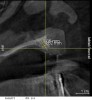

Figure 7  3-D radiographic evaluation showed a gain of about 4 mm in the thinnest area of ridge width.

Figure 7

Figure 24  Postoperative CT scan demonstrated horizontal bone regeneration.

Figure 24

Figure 25  Postoperative CT scan demonstrated horizontal bone regeneration.

Figure 25